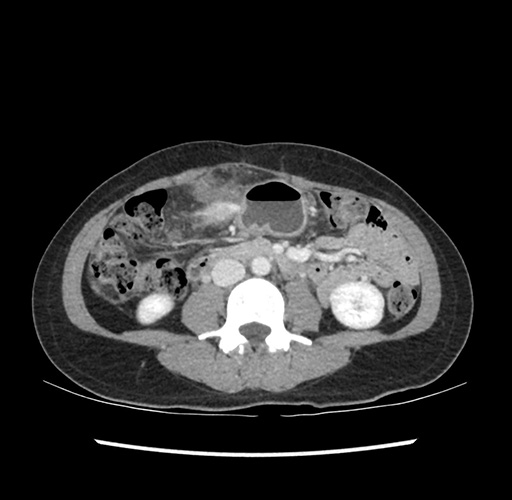

Imaging Analysis

Look through the patient's CT scan to identify any areas of concern for the necessary procedure.

Based on your CT findings, which issue(s) would give reason for "planned slowing down moment(s)" in this case?

Considering a standard left lateral sectionectomy procedure, what step(s) of the operation would you do differently in this case ?